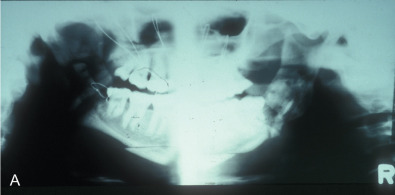

This woman had a sagittal split osteotomy done elsewhere, and ended up losing full-thickness mandible from the right parasymphyseal area to the subcondylar area. She was treated with a fibular free flap extending into the glenoid fossa, another sagittal split with mandibular advancement on the left side, and a genioplasty ( Figs. 3.9.1 and 3.9.2 ).